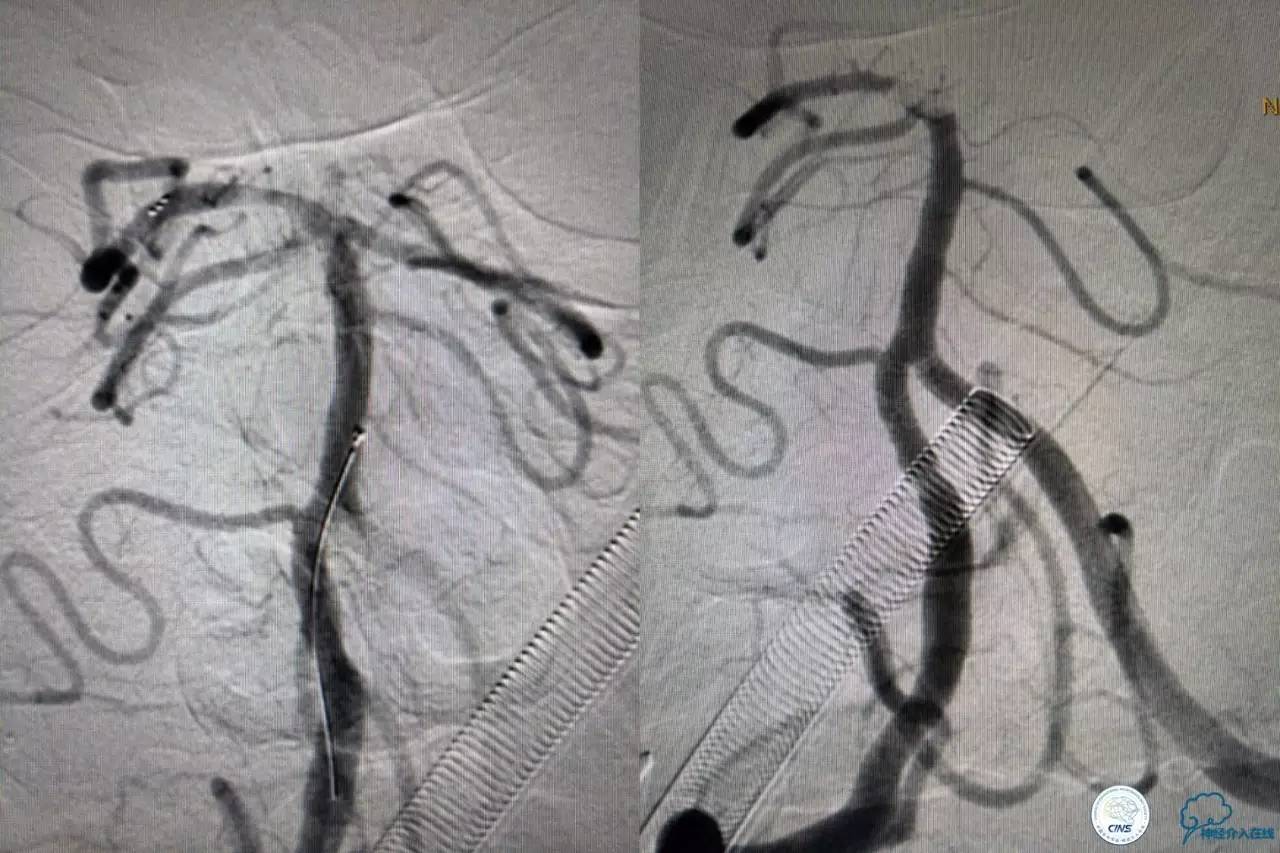

6F导引导管到位至RV2远端,rebar-18微导管及transand微导丝至右侧大脑后动脉P1远端。

solitaireAB4-20mm支架取栓。

基底动脉顶端仍有大量血栓,双侧大脑后动脉未见显影,双侧小脑上动脉再通。再次取栓?还是动脉溶栓?